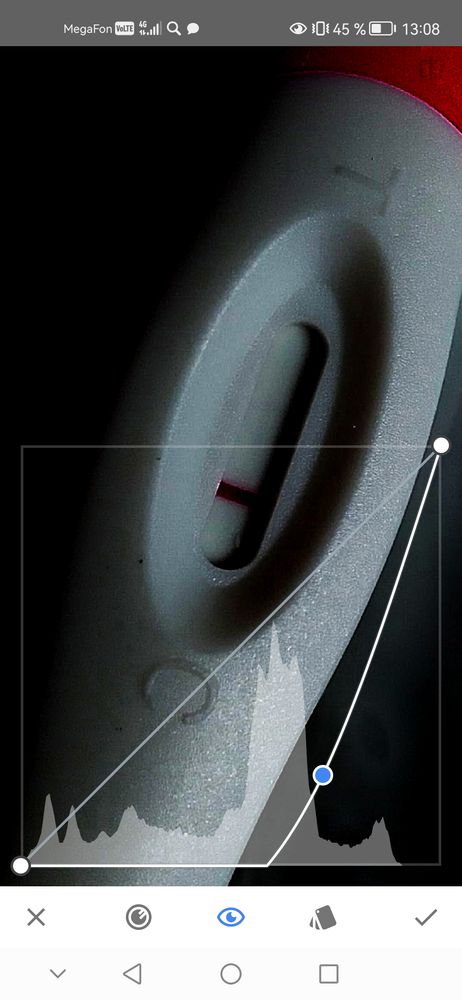

Эх совсем недавно я тусила на этом сообществе а сейчас моё чудо рядом со мной.. Но история не обо мне. Подруга 6 раз сделала перенос и хочется ваше коллективное мнение. Конечно понимаю что рано, но мы так устали ждать.. Сейчас 4 дпп посмотрите я одна вижу полоску уколов хгч не было в поддержке